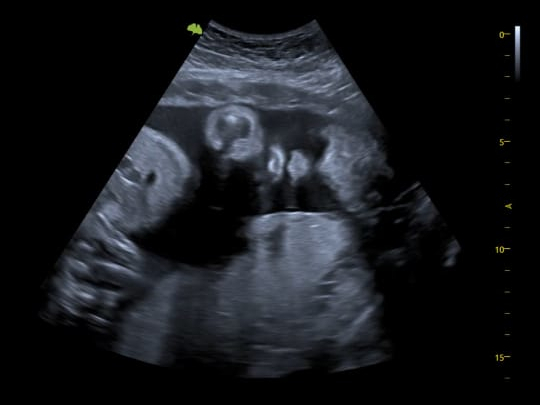

2D

General scan